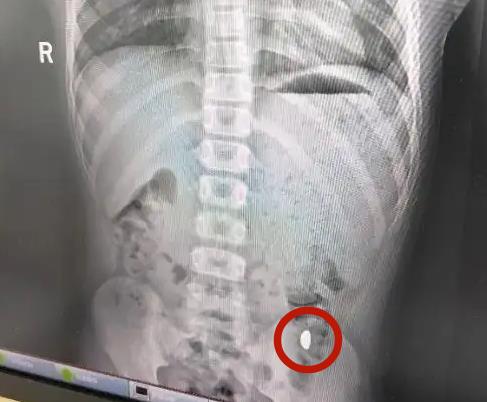

紀太太也幽默地表示,她每天提醒兒子「不能在外面拉屎,這個屎有點貴」。她在家中等了五天,希望金豆隨大便排出,期間上了兩次廁所仍未成功,最終決定帶兒子到醫院檢查。醫師表示,患童吞下的約10克黃金在胃內被檢查到,但期間沒有腹痛或嘔吐等症狀,經處理後當天即成功排出。事件曝光後,紀太太將經過分享到社群平台,引起50多萬人觀看與熱烈討論。她也提醒其他家長,家中貴重物品一定要妥善保存,避免孩子隨意把玩甚至誤吞。